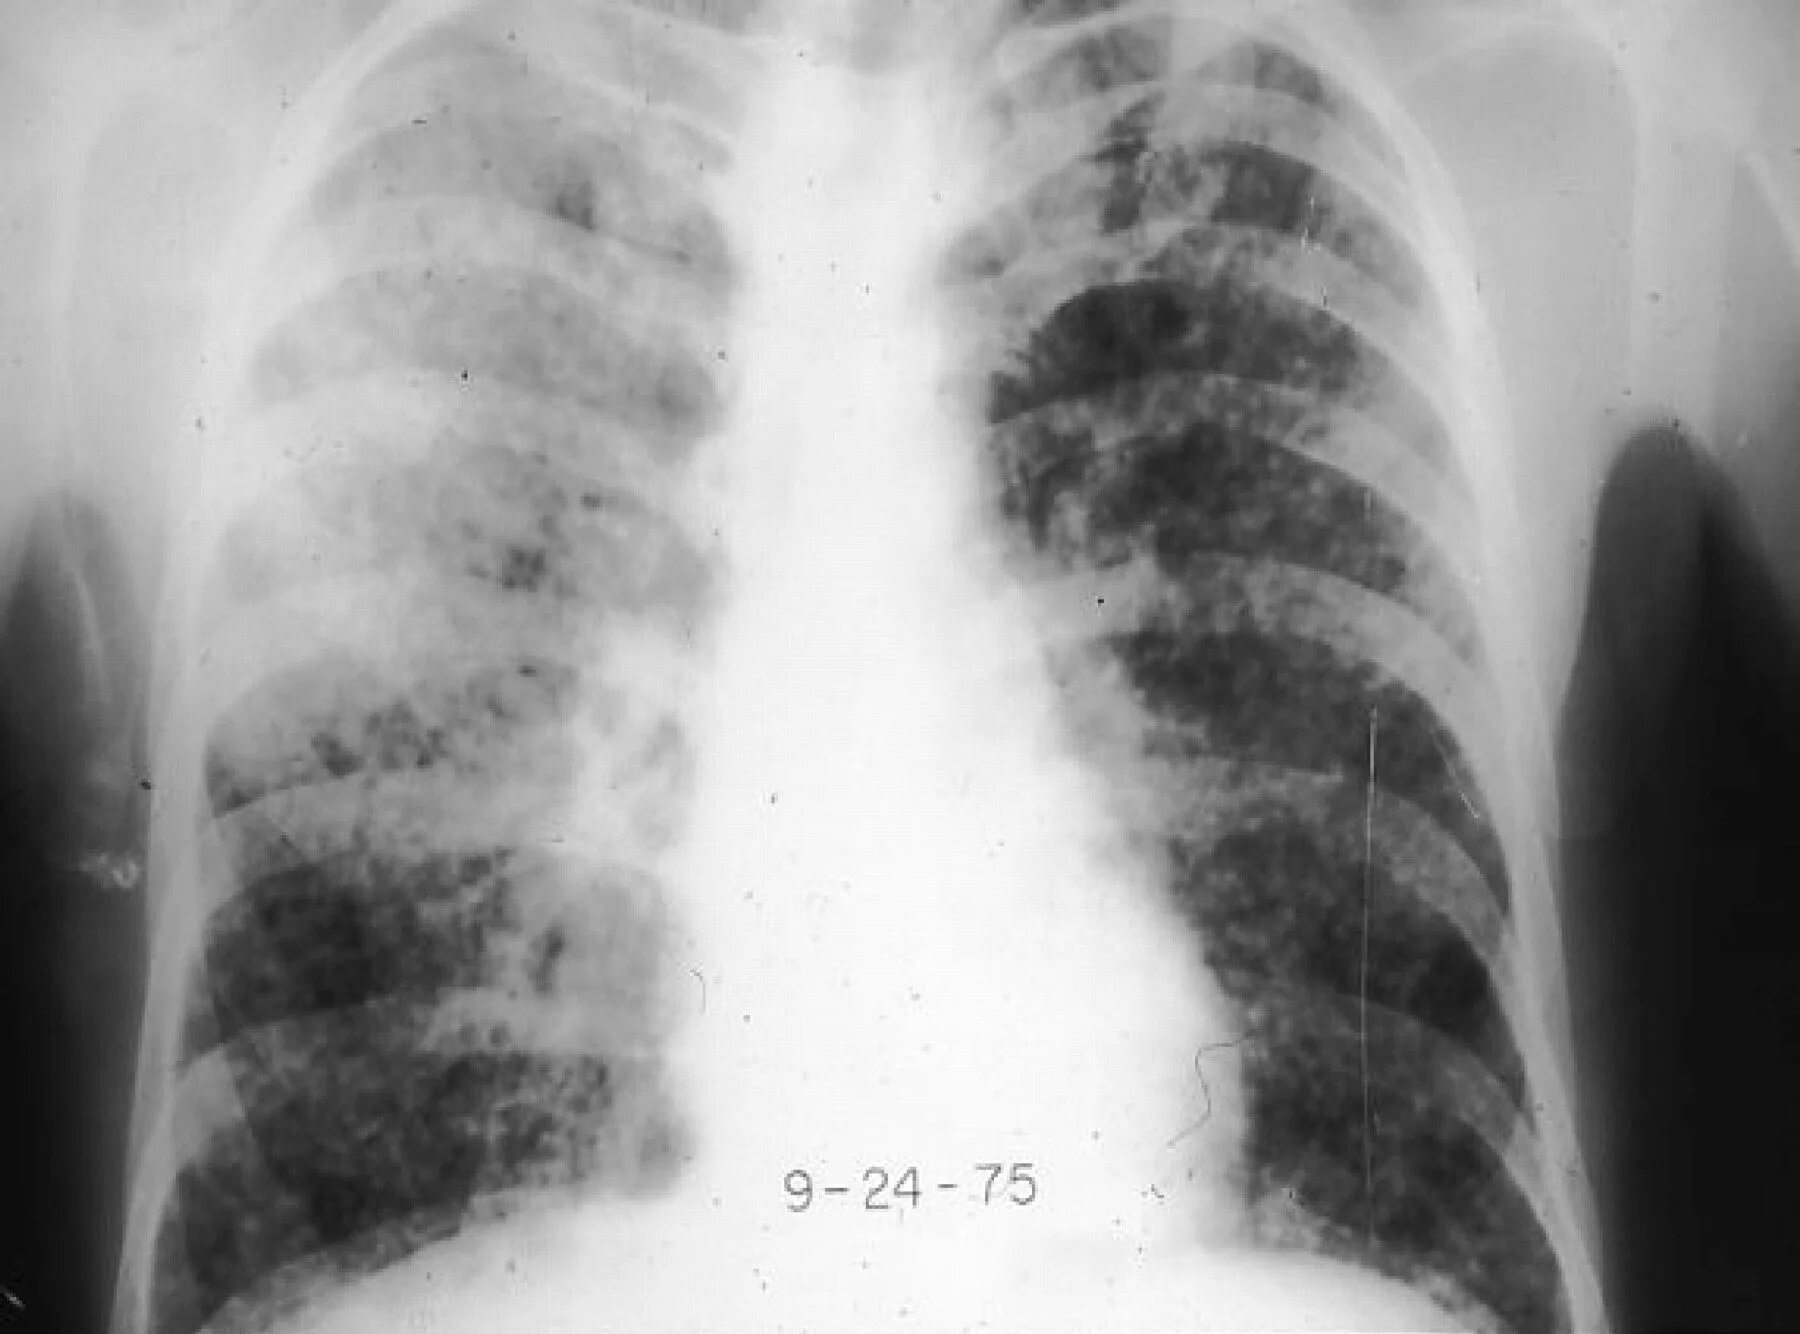

Гистоплазмоз это